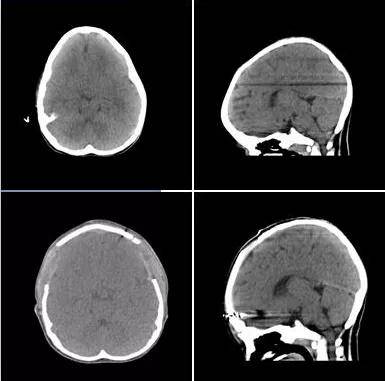

头颅ct可见额部脑外间隙增宽,额

稳定有很宽的缝隙但由于患者颅骨骨缝发育不全并未完全闭合头颅双源ct

经头颅ct三维重建,三维重建图像验证临床诊断无误,患儿的冠状缝早已经

此时的小军面色苍白,血常规显示他高度贫血,经头颅ct检查,小军左侧颞